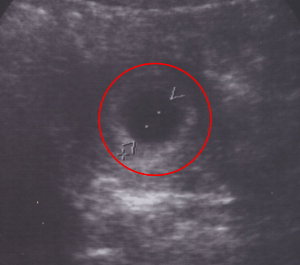

2007-05-01 六周多了 尺寸 - 5.57 mm (0.557 cm)

pig 小小惡魔第一面 爸爸沒有參與 有點鬱卒 angry 臭護士!

在第五周(含)之前,胚胎都還太小,如果你堅持要看,可以使用陰道超音波。

這時候寶寶大約一塊方塊砂糖的重量 如果去掉這時候的胚曩長相如下:

第六周:這時候的胚胎長約0.5釐米,胎體外型像隻小蝦米,顏面未完全發育,但隱約可見頭頸部、初期的大腦和胸腹部,兩側生出芽苞狀的四肢,下體外觀像尾巴,所以看起來像蝌蚪。(蝌蚪! thinking 這是在形容我們家的小小惡魔嗎?)

臍帶逐漸形成,血管生成,血液循環功能開始運作,可經由超音波看到胚胎的心跳

附加檔案 小小惡魔-20070501-web.jpg (11726 bytes) (下載次數: 5701) (小小惡魔第一張照片[真上像啊])